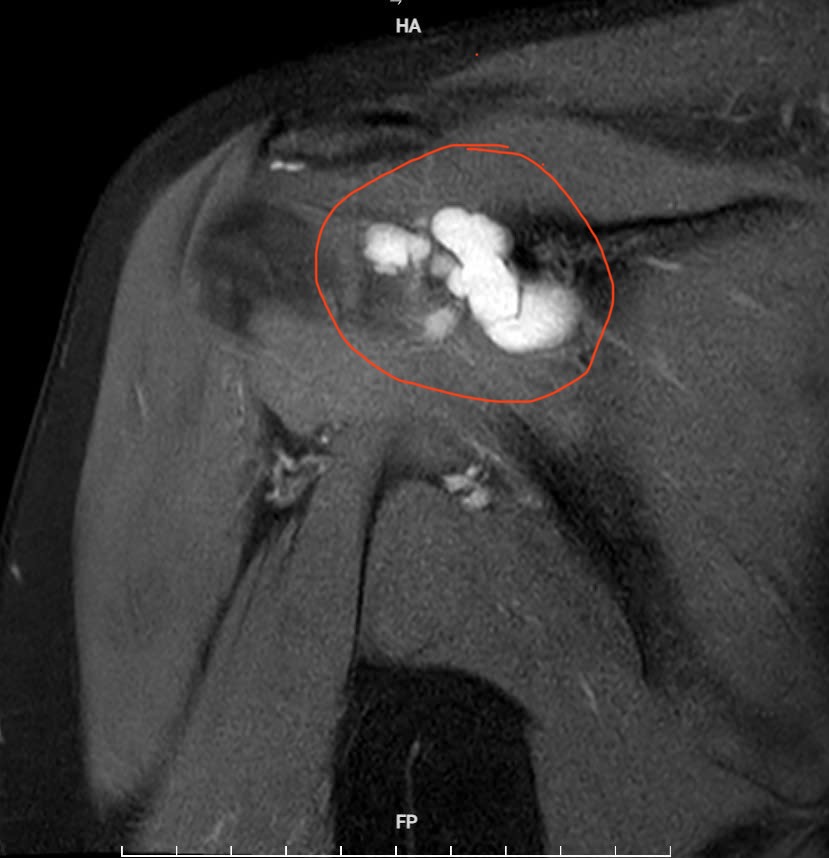

Qua thăm khám lâm sàng kết hợp chẩn đoán hình ảnh, các bác sĩ chẩn đoán bệnh nhân mắc u bao hoạt dịch khớp vai phải – một bệnh lý hiếm gặp. Kết quả chụp cộng hưởng từ (MRI) cho thấy khối u kích thước khoảng 4×2 cm gây hẹp khoang mỏm cùng vai, chèn ép các cấu trúc xung quanh.

Hình ảnh chụp cộng hưởng từ (MRI) khối u kích thước khoảng 4×2 cm gây hẹp khoang mỏm cùng vai, chèn ép các cấu trúc xung quanh.